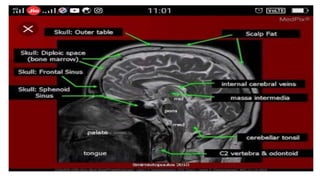

Sagittal T1 (Normal)

T1 • Provides themost anatomically-relevant images • Fluid (in CSF and orbits) is dark • Grey matter is darker than the white matter